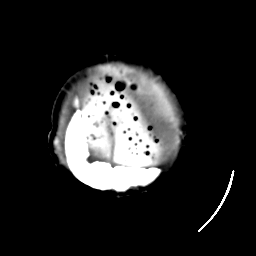

Meningioma: Roentgen-ray CT #1 -- Slice #23

[Home][Help][Clinical] Slice 23